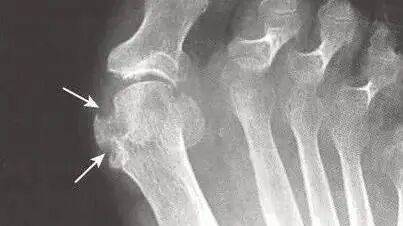

- 损伤不可逆:长期沉积会侵蚀关节软骨,形成永久性痛风石,还会堵塞肾小管,逐步损伤肾功能;